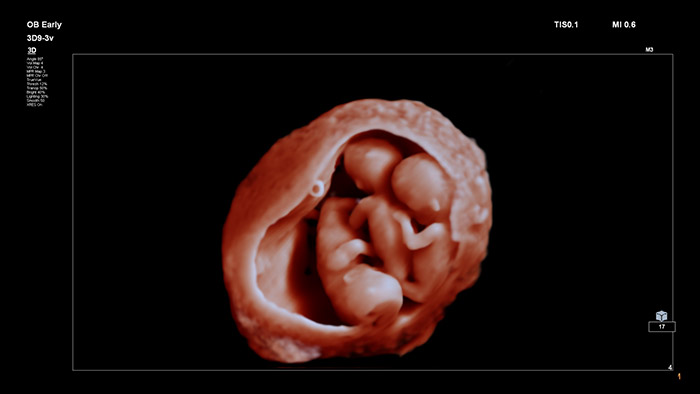

Com imagens inovadoras e altamente detalhadas, além da capacidade para manipular uma fonte de luz virtual e flexível, o TrueVue fornece aos médicos e às grávidas imagens extremamente realistas do feto durante a gravidez.